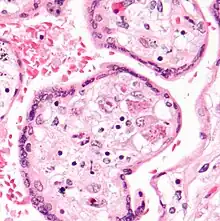

CMV infection can be demonstrated microscopically by the detection of intranuclear inclusion bodies. On H&E staining, the inclusion bodies stain dark pink and are called "owl's eye" inclusion bodies.[45]

Lytically replicating viruses disrupt the cytoskeleton, causing massive cell enlargement, which is the source of the virus' name.